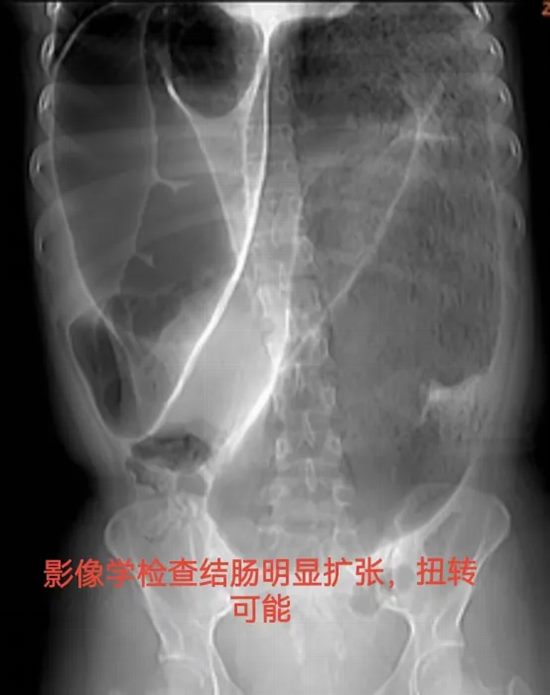

病情简述:19岁女性,间断腹痛腹胀4年,辗转求医未果。此次因急性加重急诊入院。

诊疗破局:CT提示结肠梗阻,非手术减压无效。急诊剖腹探查发现元凶是罕见的“结肠重复畸形”并扭转。及时的手术不仅解除了急性梗阻,切除了病变肠段,更找到了困扰她4年的病根。术后患者恢复良好,已回归正常生活。

技术体现:面对罕见急腹症,果断的手术决策与扎实的探查功底,是挽救患者、明确病因的根本。